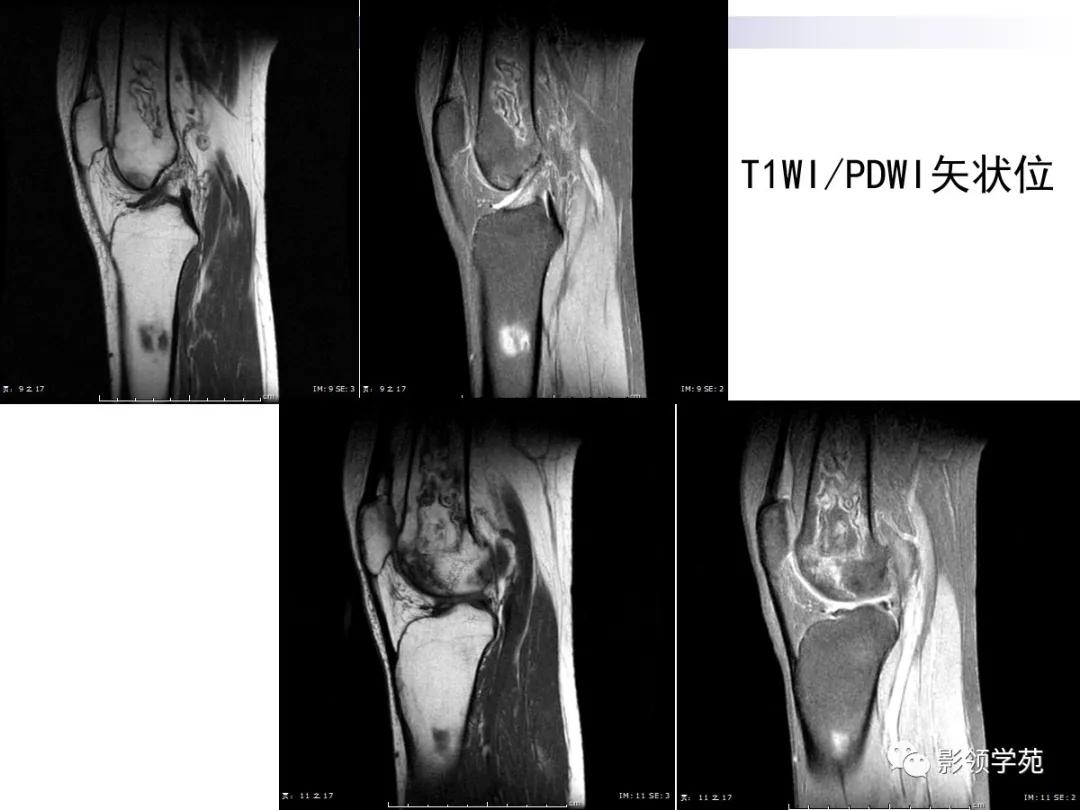

病例2:女性,45岁,病史:临床诊断SLE10年,膝关节疼痛4年。

MRI:呈不规则片状、斑片状混杂信号,病灶中央T1WI呈等、低信号,T2WI等、高信号,内部信号不均匀。

MR:T1及T2均呈不规则的混杂片状低信号影,周围可见线状低信号单环征

患者因临床反复发作,新旧病灶同时存在,所以骨梗死以多发性、多形性、多期表现并存。